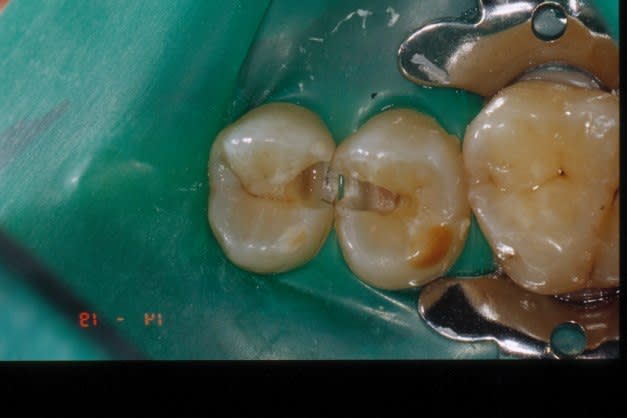

Sur une cavité profonde, un composite vaut un nécro. Combien trouve-t-on de 4èmes consécutifs !

donnot, un composite direct n'est pas indiqué pour les grosses cavités profondes, et quand il l'est , il doit être fait dans les règles de l'art. càd, digue, protocole rigoureux , etc. si c'est trop gros, c'est inlay. je n'ai plus de machine à Ag depuis qu'ils ont interdit le vrac: si tu crois que je fabrique des nécros à longueur de journée, tu te trompes. avant de critiquer un matériau, commence par bien cerner son indication.

donnot, il m'est arrivé de réaliser carrément des coiffages au composite, d'autres personnes ici en ont déja parlé, collage d'inlay sur pulpe exposée, au variolink: je te garantie qu'un test de vitalité est réalisé tout les six mois sans souci depuis des années.

Je ne voulais, en effet, que parler d'expérience clinique, donc de toxicité pulpaire. On voit des amalgames très anciens, très proches de la pulpe et quasiment pas de mortifications.

Par contre, avec des composites, il est fréquent de trouver des gangènes, surtout sur les incisives sur lesquelles il n'y a pas vraiment d'autre possibilité.

J'ai aussi essayé des coiffages et j'ai été étonné de constater que la vitalité pulpaire est mieux assurée sur une pulpe exposée que sur une pulpe trop proche mais non ouverte. Pourquoi ? Je ne sais pas. Mais je n'utiliserais jamais une telle dent en support de conjointe.

Quand c'est possible, je préfère sans problème un inlay scellé au verre ionomère ou au polyphosphate.